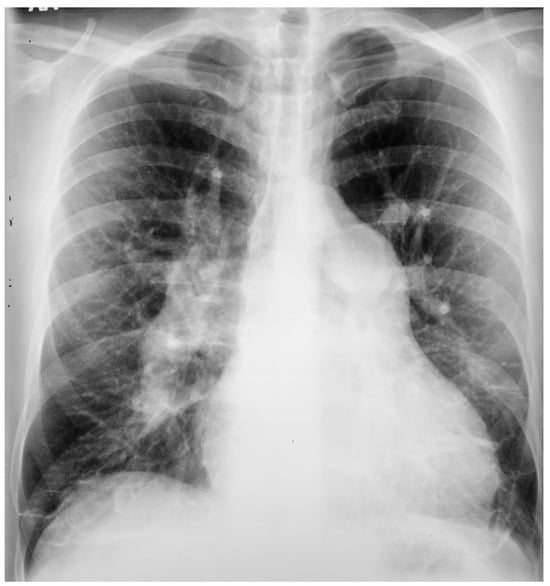

Figure 19.

Posteroanterior chest X-ray of severe pulmonary stenosis: this chest X-ray is of a 31-year-old female who presented with worsening exertional dyspnea over the last two years. Her exam revealed elevated jugular venous pressure with prominent A wave. She was noted to have a right ventricular lift with a grade 4/6 systolic ejection murmur best heard at the left upper sternal border. The chest X-ray is well centered and there is a good inspiration. The cardiothoracic ratio is normal. The pulmonary trunk is enlarged (its right border is outlined by blue dots as it passes over the left bronchus). The left pulmonary artery branch that is indicated by two red arrows is also enlarged. Her echocardiogram revealed severe pulmonary valve stenosis with peak gradient 68 mmHg and mild pulmonary valve regurgitation. She subsequently underwent balloon valvuloplasty with reduction of her peak gradient to 24 mmHg. Her symptoms of dyspnea had resolved a few months post-procedure.